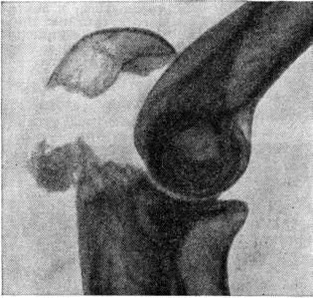

Основной рентгенологическое признак нарушения целости кости — линия Переломы Большое диагностическое значение имеет смещение отломков, наличие которого настолько бесспорно доказывает нарушение целости кости, что надобность в дифференциальной диагностике отпадает. Как бы подробно ни была описана рентгенологическое картина Переломы, наиболее полное и правильное представление о степени и характере смещения отломков врач может составить лишь при непосредственном просмотре снимков. Захождение отломков одного за другим при продольном смещении на рентгенограмме в одной проекции может сопровождаться наслоением теней концов отломков — так называемый суперпозицией теней. В этом случае точное определение смещения отломка возможно на основании данных снимков во второй проекции. При Переломы плоских костей (лопатка, ребра, таз и другие), при которых по техническим причинам производство снимка во второй проекции затруднено, суперпозиция отломков часто является единственным достоверным признаком Переломы Распознавание продольных смещений с расхождением отломков обычно не представляет каких либо затруднений. Подобного рода смещения наблюдаются при Переломы надколенника с разрывом связочного аппарата, локтевого отростка, вертелов бедра, отрывах костных выступов, к которым прикрепляются мышцы, сокращающиеся при повреждениях и приводящие к расхождению. Интерпозиция мягких тканей между отломками костей при рентгенологическое исследовании не распознается. Различные виды Переломы в наиболее информативных проекциях представлены на рисунок 4—11.